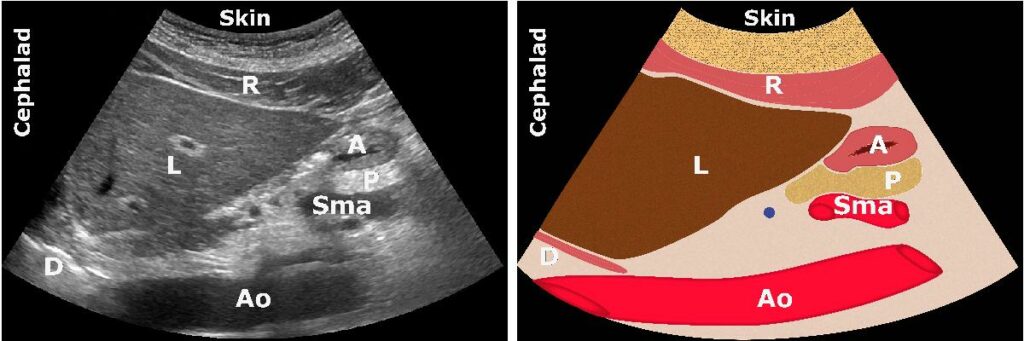

2. ANATOMİ

A: Antrum; Ao: Aort; C: Kolon; L: Karaciğer; P: Pankreas; SI: İnce bağırsak; Sma: Süperior

mezenterik arter; Smv: Süperior mezenterik ven

Mide antrum

Sonografik incelemeye en uygun olanıdır ve tüm midenin içeriğini doğru bir şekilde yansıtır.

Karaciğer (önde) ve pankreas (arkada) arasındadır.

İçi boş karakteristik 5 katmanlı duvarı vardır.

Genellikle yüzeysel yerleşimlidir (3-4 cm)

Önemli belirteçler

- Karaciğerin sol lobu

- Pankreas

- Aort